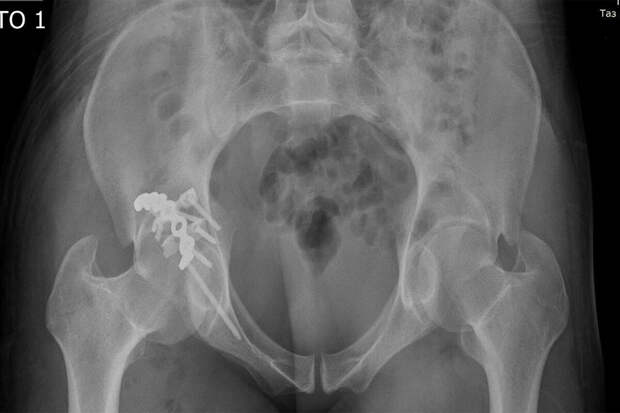

Жительница Хабаровска получила травму на производстве, на нее упала бетонная плита весом четыре тонны. Пострадавшая получила сложный перелом тазовых костей, переломы обеих ключиц и голени.

Хирурги-травматологи прооперировали россиянку, успешно соединили и скрепили поврежденные кости специальными креплениями. Женщина находится под наблюдением медиков и восстанавливается после хирургического вмешательства.